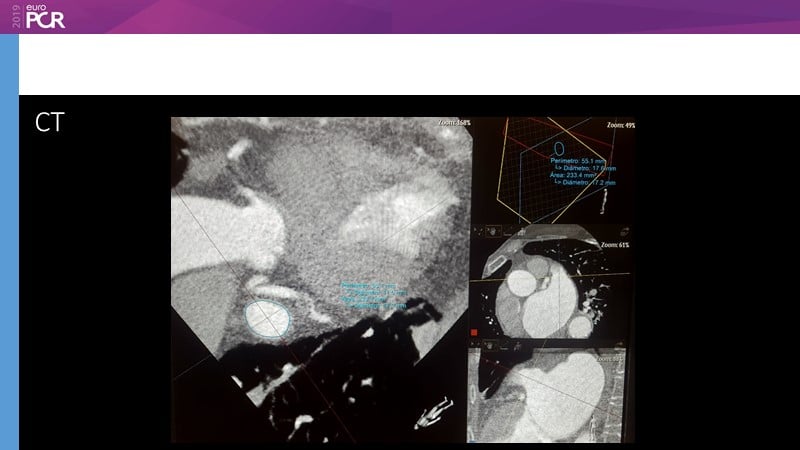

Pre-procedure planning

Previous Next